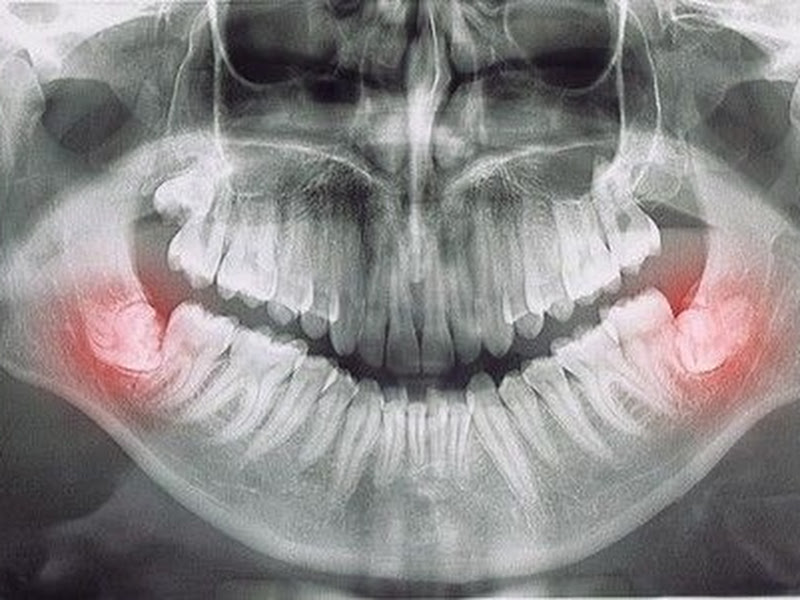

“Sem comentários para agradecer e elogiar o tanto que merecem! Sou muito grata a Deus por ter “caído” na busca desse consultório! Outrora, eu havia tentado tirar meu siso por umas 5x, a dentista não conseguia, a anestesia nao pegava, foi uma tortura, tomei antibiótico antes, depois, durante e nada, foram uns 7 dias pra mais! Deixei pra lá e depois de um tempo, eu procurei tratamento, bem traumatizada, confesso, iria fazer no particular e ao ver a boa fama do dr, imaginei que só conseguiria pagar vendendo um órgão hahahhaah não fui cobrada na avaliação, a Rita de uma elegância ímpar, e o dr? O que falar dele? Sem comentários pra fineza, simpatia, empatia, transparência e propriedade no que fala e mostrando que nasceu pra fazer o que faz. Com muito medo, voltei pra tirar esse dente que me tirava o juízo hahaha tomei remédio antes e estou tomando durante, foi tudo um SUCESSO, sem dor com uma anestesia, em 1 dia, e em menos de 1 hora (eram 2), e por um valor que até agora estou muito feliz pq coube e foi mais baixo do que com dentistas e não com bucomaxilo. Agradeço demais a todos da clínica, a Rita, ao dr Cesar, ao dr que o auxiliou, a Andreza- sem palavras. Dr. obrigada por tudo e por se deixar cumprir seu propósito na terra e ajudar tantas vidas!”

Dr. César é um excelente profissional, antes de conhecer a clínica estava com muito medo de extrair os meus sisos, mas ele me passou confiança e tirei 3 sisos, a cirurgia e o pós operatório foi muito tranquilo. Recomendo muito.

Dr César Donadio é um profissional de primeiro mundo. Extraiu 3 dentes meus sem nenhuma dor. Indico e recomendo por onde eu passar. Merece aplausos pelo seu profissionalismo!!